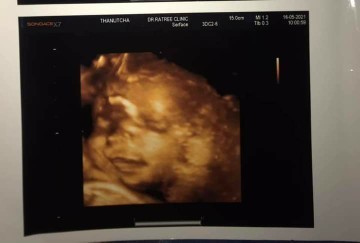

ภาพซาวด์4มิติ

ขอดูภาพซาวด์4มิติ ของแม่ๆท่านอื่นหน่อยคะ บ้านนี้ซาวด์ปัยน้องยิ้มเล่นไปด้วย ให้ทายว่าน้องเปนผญ.หรือผช.😊